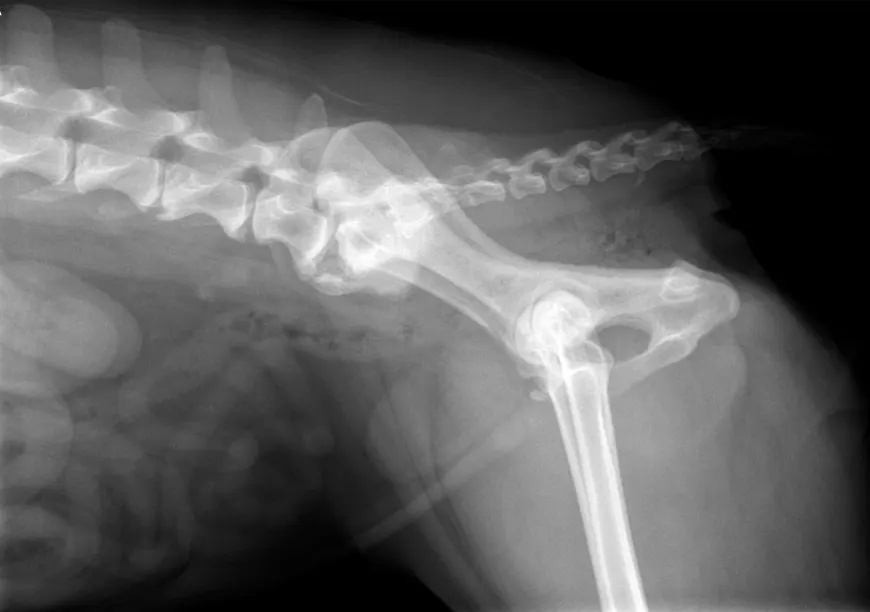

Para diagnosticar muchas enfermedades, saber el estado de salud de nuestros animales e instaurar algunos tratamientos..

Ecografía / Ecocardiografía. En la práctica diaria necesitamos en numerosas ocasiones realizar ecografías abdominales, torácicas, y de otros..